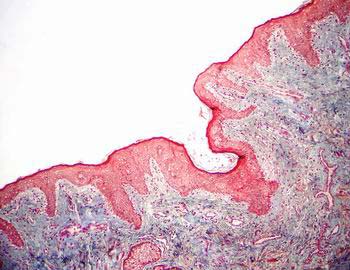

presentamos un fragmento de piel fina para estudiar tanto el conjuntivo

laxo común que aparece justo por debajo de la capa epitelial

o epidermis constituyendo la dermis papilar, como el tipo de conjuntivo

fibroso denso no ordenado, que con una mayor proporción de fibras,

conforma por debajo la dermis reticular. El plano mas profundo es la

hipodermis con una gran abundancia de tejido adiposo. Este preparado

nos permite también analizar la estructura de la epidermis o

epitelio de la superficie de la piel.

Visión específica: se evidencia a mayores

aumentos la diversa arquitectura de las tres regiones. En la dermis

papilar fibras más finas y fundamentalmente orientadas perpendicularmente

hacia la lámina epitelial pavimentosa estratificada queratinizada

y entre las que se observan numerosas células y capilares. Por

debajo se evidencia el carácter fasciculado de la dermis reticular,

con haces mas gruesos de las fibras de colágena separados por

material no teñido que corresponde con la sustancia fundamental;

y entremezcladas se observan aisladas células débilmente

teñidas, vasos, glándulas sudoríparas y glándulas

sebáceas asociadas a folículos pilosos. En la dermis profunda

se acumulan grandes cantidades de células adiposas uniloculares,

rodeadas de un conjuntivo vascularizado.

El tejido epitelial que cubre la superficie libre de este preparado,

la epidermis, es un epitelio plano pluriestratificado y queratinizado.

La capa mas profunda esta constituida por una fila de células

cúbicas, el estrato basal, por encima un numero variable de capas

de células poliédricas que progresivamente se van aplanando,

el estrato espinoso, y ya en superficie las células mas diferenciadas

en su proceso madurativo las del estrato granuloso y del estrato córneo.

En este caso es una piel fina por lo que la capa superficial de células

anucleadas o escamas córneas no es muy amplia.